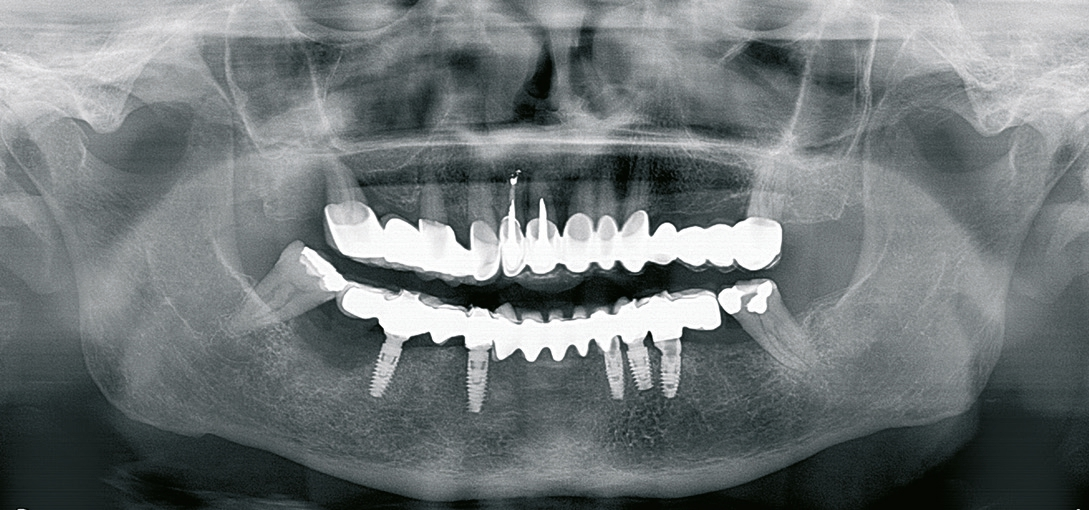

Für die Suprakonstruktionen wurde das Sekundärgerüst auf Abutment-Niveau gefräst. Der Patient bekam im Oberkiefer ein System mit interner Sechskantverbindung (Abb. 9-16). Die Patientin im Unterkiefer bekam ein System desselben Herstellers mit konischer Abutmentverbindung (Abb. 1-8). Davon ist ein Implantat noch in der Einheilphase verloren gegangen. Der betroffene Kiefer konnte trotzdem mit fünf Implantaten versorgt werden. Vom Prinzip „all-on-4“ wurde bewusst Abstand genommen. Ebenso wurde auch auf geneigt gesetzte Implantate verzichtet. Die Implantate, die abgewinkelte Abutments bekamen, wurden nach den prothetisch und anatomisch günstigsten Knochenverhältnissen gesetzt.

Die Gerüste, welche auf Implantatniveau hergestellt wurden, werden überwiegend für den Oberkiefer geplant. Dort empfiehlt sich auch der klassische Sechskant, der leicht gefräst werden kann. Im Unterkiefer führt eine Versteifung des Kiefers durch lange rigide Spannweiten zu Spannungen. Solche Spannungen im Kiefer (Torsionskräfte) kommen bei der Mastikation zustande und auch bei Parafunktionen oder Pressen und können langfristig zu Überbelastungen der Implantate führen. Hier empfehlen sich konische Verbindungen und Multiunit-Abutments. Durch die konische Verbindung ist eine Lockerung des Abutments unwahrscheinlich. Durch die Multiunit-Abutments sind die Torsionskräfte am Unterkiefer ausgeglichen, indem die Verbindung zum Sekundärgerüst als Puffer fungiert (Abb. 4). Sollten diese Kräfte zu hoch werden, lockern sich ein oder zwei Schrauben zwischen Abutment und Prothetik. Es gab nie einen Fall, in dem mehr als zwei von sechs Schrauben locker waren und keinen Fall in dem eine Brücke locker wurde. Kombiniert mit einer Komposit-Verblendung ist diese Lösung für den Unterkiefer optimal. Der Oberkiefer kann, in Fällen in denen beide Kiefer behandelt werden, keramisch verblendet werden.

Die Verblockung aller Implantate miteinander zeigt sehr hohe Stabilität. Das periimplantäre Gewebe ist auch nach vier Jahren stabil. Im Zeitraum der Nachkontrollen gab es keine Implantatverluste. Ähnliche Ergebnisse sehen wir auch bei den all-on-4 Protokollen. Das Setzen von 5-6 Implantaten pro Kiefer erhöht zwar die Kraftverteilung, dient aber primär der Erweiterbarkeit der Versorgung bei potenziellen Verlusten und der optimalen Mastikation dadurch dass alle Gegenkiefer teilbezahnt und implantologisch festsitzend versorgt waren.